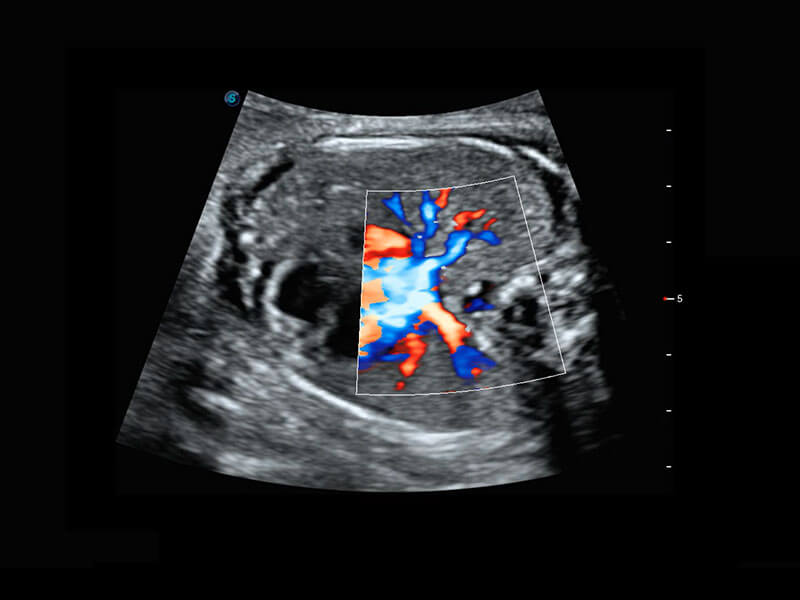

胎儿体循环

光影成像-孕囊